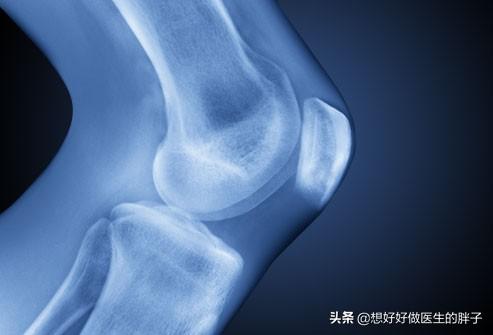

Es gibt ein klapperndes Geräusch, wenn das Kniegelenk gebeugt und gestreckt wird, ein Geräusch, das uns manchmal das Gefühl gibt, auf Schnee zu treten, ein raschelndes Geräusch.Vor allem, weil der Knorpel in den Gelenken nicht so glatt ist, wie er sein sollte.Die Begründung ist so gut wie die Begründung für die Kugellager in unseren Fahrrädern, die Körnung haben, sie ist sehr gut nachvollziehbar.

- Knorpeldegeneration

Auf der Oberfläche der Knochen des Kniegelenks, gibt es eine Schicht von Knorpel befestigt, gemeinsam in das Kniegelenk unter übermäßigem Druck Last, wird wegen der Abnutzung des Knorpels, in unserer Aktivitäten, die Schmerzen; Knorpel Verschleiß allmählich verschlimmert, wird dazu führen, dass Oberschenkelknochen und Wadenbein harte Kollision, den Verlust der Stabilität des Gelenks, und allmählich gibt es Osteomalazie, Blutzirkulation Verschlechterung, die Kühle und die knallenden Ton ist unvermeidlich.

In unseren Kniegelenken ist die Gelenkfläche mit feinem, glattem Knorpel überzogen, damit sie sich reibungslos bewegen kann. Wenn die Gelenkfläche aufgrund von Verletzungen oder Überbeanspruchung abgenutzt ist, wird sie uneben, und der Knochen gleitet bei der Bewegung des Gelenks auf der unebenen Fläche, was zu einem Klappern führt. Bei der Bewegung des Gelenks gleitet der Knochen auf der unebenen Gelenkfläche und es entsteht ein klapperndes Geräusch, das von starken Schmerzen begleitet sein kann.